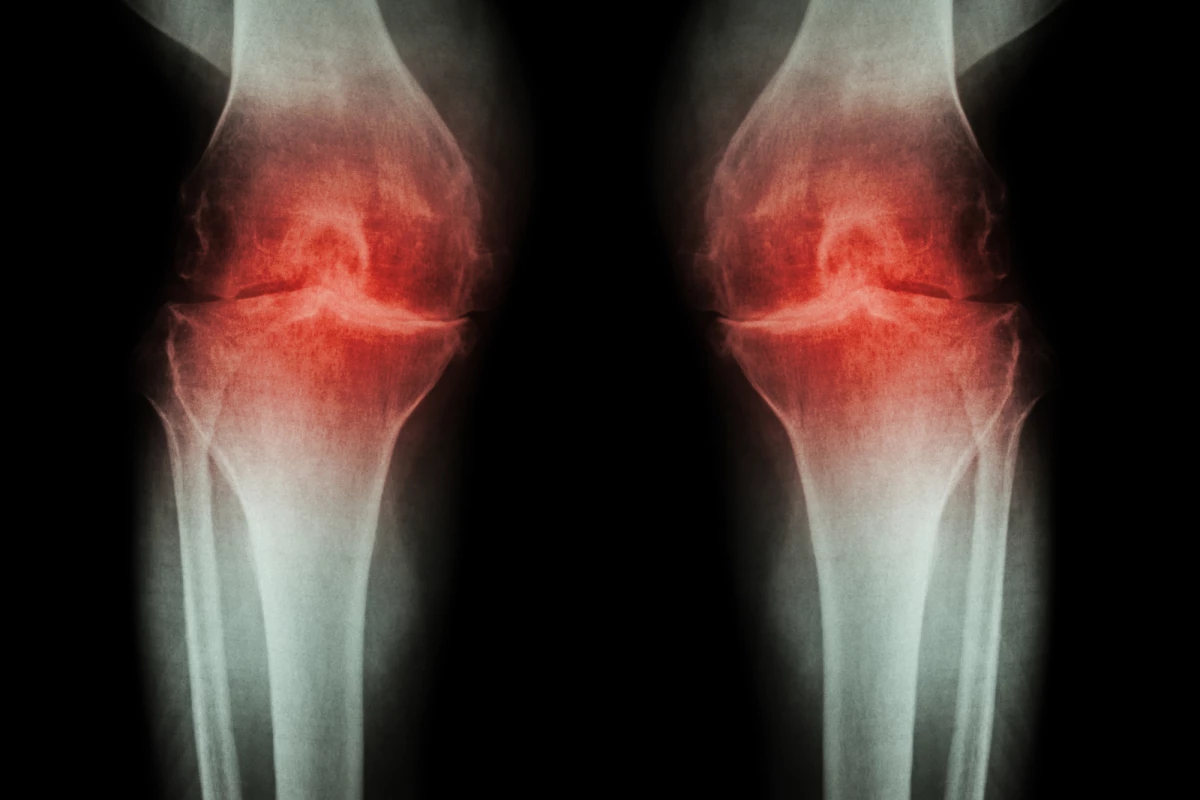

As we age, our bodies gradually lose the ability to repair damage as fast as it needs to. That means that tissues subjected to high-intensity long-term use, such as cartilage in joints, are especially prone to wearing out. That manifests itself in the common condition of osteoarthritis, resulting in pain when that joint moves.

After six weeks, the team examined the cartilage in the rats’ knees. The control group didn’t do too well – in that time, the disease had progressed from stage 2 to stage 4. But in the test group, the disease hadn’t just slowed down, it had reversed from stage 2 back to stage 1. This meant the cartilage had gotten thicker, with fewer cells dying and more of them actively growing.